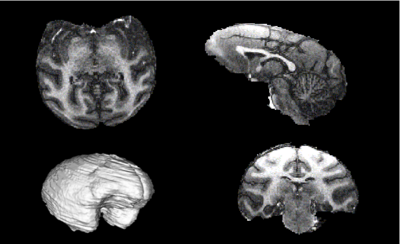

- Optimize the EM Brain Classifier in Slicer on MRI images of rhesus macaques

- Study data on 8 subjects at two time points (alcohol naive and post-induction) organized

- Study data has been skull stripped, ECC masks created, and GM/WM/CSF priors registered to each subject. The ECC masks may need some hand editing and, as a result, the atlas-priors to subject registration is poor in several subjects.

- Nonlinear registration of atlas priors completed using Slicer